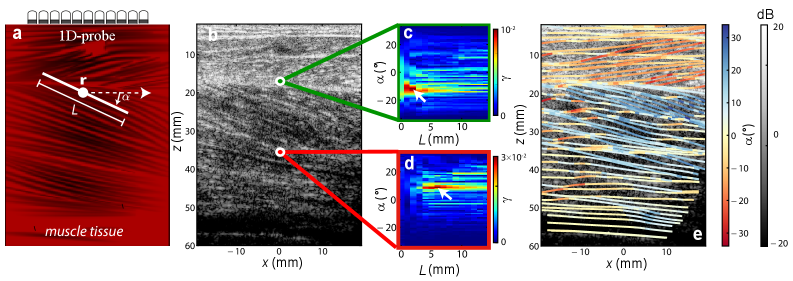

As a proof-of-concept, we will show how it can be used for mapping the local anistropy of a fibrous medium. This information is particularly relevant for muscle tissues in ultrasound imaging in order to diagnose neuromuscular 38 or myocardial 39 diseases. The experiment is carried out on a human calf, in-vivo, the fibers of which are partially visible on the ultrasound image displayed in Fig. 4b. This image is built from the reflection matrix 𝐑\mathbf{R} recorded using a linear phased array of 256 transducers over the [5.5; 9.5] MHz frequency bandwidth (Methods, Extended Data Tab. 1). In order to image fibrous tissues, the fingerprint matrix is defined as a free-space reflection matrix 𝐑0(𝐪)\mathbf{R}_{0}(\mathbf{q}) associated with a reflecting 1D mirror whose state 𝐪\mathbf{q} is described by its position 𝐫\mathbf{r}, its orientation α\alpha and its dimension LL (Fig. 4a). The dictionary of fingerprint matrices 𝐑0(𝐪)\mathbf{R}_{0}(\mathbf{q}) is constructed numerically (Methods).

The scalar product of the recorded reflection matrix 𝐑\mathbf{R} with the fingerprint matrix 𝐑0\mathbf{R}_{0} (Eq. 2) provides a likelihood index γ(𝐫,α,L){\color[rgb]{0,0,0}\gamma}(\mathbf{r},\alpha,L) with respect to the parameters α\alpha and LL at each point 𝐫\mathbf{r} in the image (Eq. 2). The dependence of the γ{\color[rgb]{0,0,0}\gamma}-map with respect to parameters α\alpha and LL is shown for two points 𝐫\mathbf{r} in the field-of-view in Figs. 4c and d. The maximum value of this quantity gives the orientation αopt(𝐫)\alpha_{\textrm{opt}}(\mathbf{r}) and the local correlation length Lopt(𝐫)L_{\textrm{opt}}(\mathbf{r}) of the fibrous medium at each point 𝐫\mathbf{r}:

{αopt(𝐫),Lopt(𝐫)}=argmax{α,L}[γ(𝐫,α,L)]\{\alpha_{\textrm{opt}}(\mathbf{r}),L_{\textrm{opt}}(\mathbf{r})\}=\arg\max_{\{\alpha,L\}}\left[\gamma(\mathbf{r},\alpha,L)\right] (7)

The size and orientation distribution of the fibers provide a vector representation of the fibers superimposed to the confocal image in Fig. 4e. A very good agreement is found between the visual appearance of the fibers on the ultrasound image and their vector representation provided by the fingerprint operator.

Refer to caption

Figure 4: Revealing the local architecture of fibers in muscle tissue. a, Sketch of the experimental configuration: An array of transducers is placed in contact with the calf of a healthy patient. The fingerprint operator 𝐑0(𝐪)\mathbf{R}_{0}(\mathbf{q}) here corresponds to a set of reflection matrices associated with a mirror of size LL and orientation α\alpha simulated for each pixel 𝐫\mathbf{r} in the medium considered as homogeneous (c0=c_{0}= 1580 m/s). b, Ultrasound image of the calf in dB. c, d, Likelihood index γ\gamma in the (L,α)(L,\alpha) parameter space for two positions yielding different values for the local correlation length LL and fiber orientation α\alpha. The white arrows indicate the optimal length LoptL_{\textrm{opt}} and orientation αopt\alpha_{\textrm{opt}} at each position. e, Vector representation of the fibers deduced from the orientation distribution αopt(𝐫)\alpha_{\textrm{opt}}(\mathbf{r}) encoded with the color scale displayed on the right.